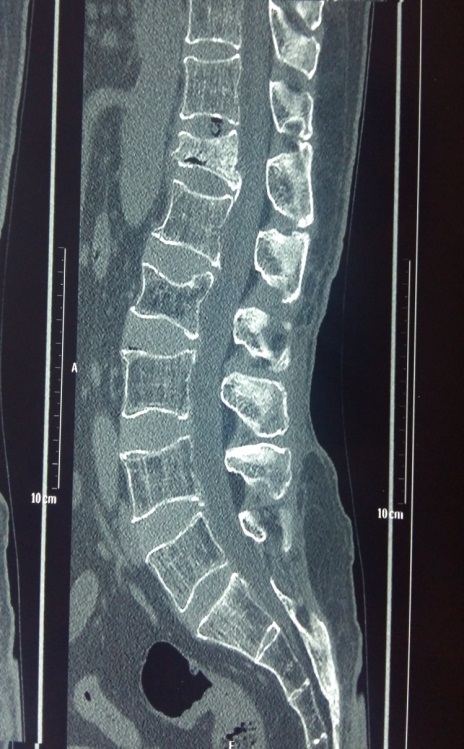

Preop MRI of multiple vertebral collapse

osteoporosis

Postop Xray of the bone operated with kyphoplasty